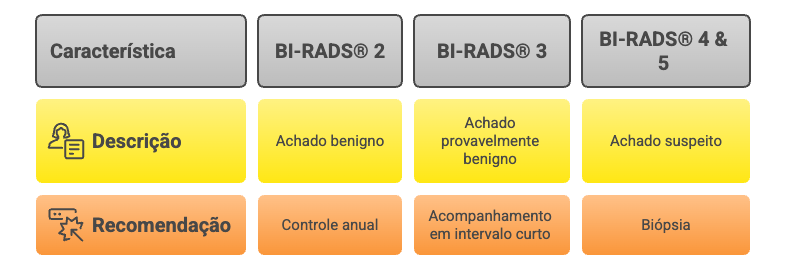

Ao receber o laudo do seu exame das mamas, você provavelmente verá a sigla BI-RADS®, seguida por um número de 0 a 6. Este é um sistema padronizado mundialmente que classifica os achados dos exames de imagem das mamas e orienta a conduta médica. No contexto das calcificações, as categorias mais comuns são:

-

BI-RADS® 2 (Achado Benigno)

Geralmente se refere a macrocalcificações ou microcalcificações com características tipicamente benignas. A recomendação é seguir com o controle anual.

-

BI-RADS® 3 (Achado Provavelmente Benigno)

Indica que o achado tem uma chance de malignidade muito baixa (menor que 2%), mas o radiologista sugere um controle em um intervalo menor, geralmente em 6 meses, para garantir que não haja mudanças.

-

BI-RADS® 4 e 5 (Achado Suspeito)

Estas categorias indicam que as calcificações têm características que levantam suspeita. A chance de ser câncer varia, mas a recomendação é realizar uma biópsia para um diagnóstico definitivo.